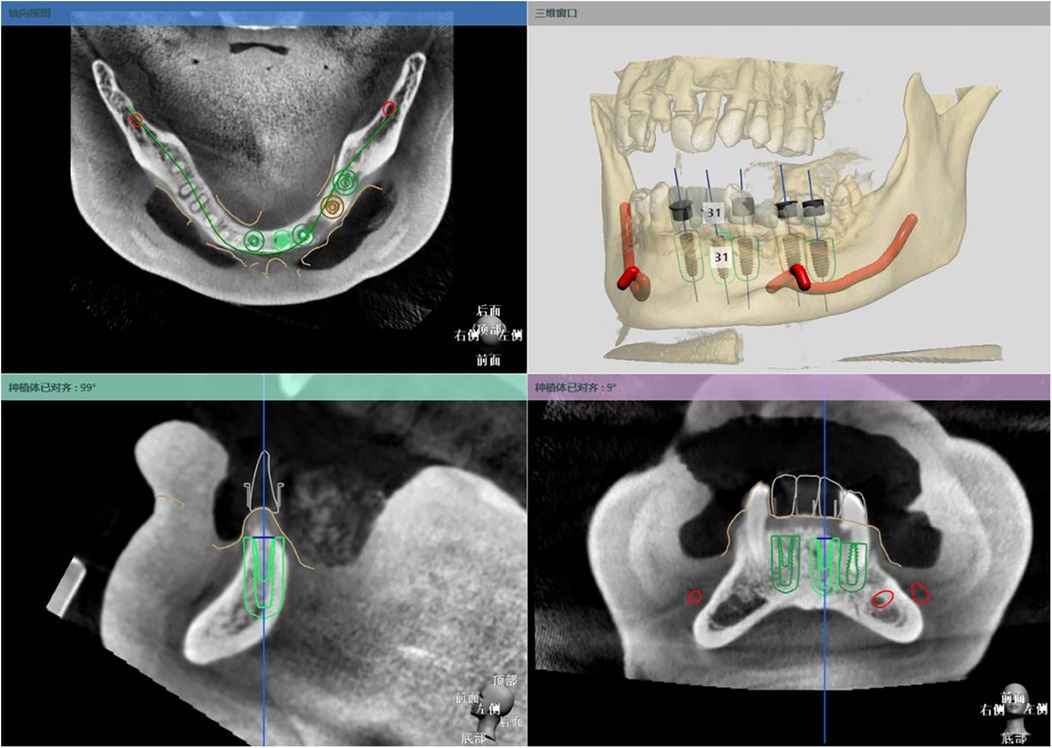

Background: Digital guided implantology improves safety and precision compared to freehand methods. A survey indicated that half-guided templates are more commonly used than full-guided ones in China. This study aims to assess the accuracy of implant placements using half-guided and full-guided digital surgical templates, considering factors like jaw location, tooth position, support type, implant timing, and bone density. Methods: 87 implants (52 half-guided, 35 full-guided) were evaluated by comparing pre-and postoperative CBCT scans to measure deviations in coronal, apical, depth, and angular positions. Bone density was also assessed in relation to the implant deviations. Results: The findings revealed that the half-guided group exhibited significantly greater deviations in several areas: maxillary angular deviations, anterior coronal and depth deviations, posterior depth deviations, tooth-supported guide depth deviations, immediate implant coronal and angular deviations, and delayed implant depth deviations (P < 0.05). No significant differences were noted in other measurements. In the bone density analysis, only the full-guided group showed a significant negative correlation between bone density and apical deviation (P < 0.05). Conclusion: Based on statistical results, power calculations, and subgroup effect sizes, the following clinical recommendations are derived: Half-guided templates, owing to their superior cost-effectiveness in fabrication time and cost, are recommended for use in mandibular posterior regions, mucosa-supported templates, delayed implantations, and clinical scenarios with uneven bone density distribution at implant sites. In contrast, full-guided templates are more suitable for maxillary implantations, anterior regions, tooth-supported templates, immediate implantations, and sites with homogeneous bone density distribution.